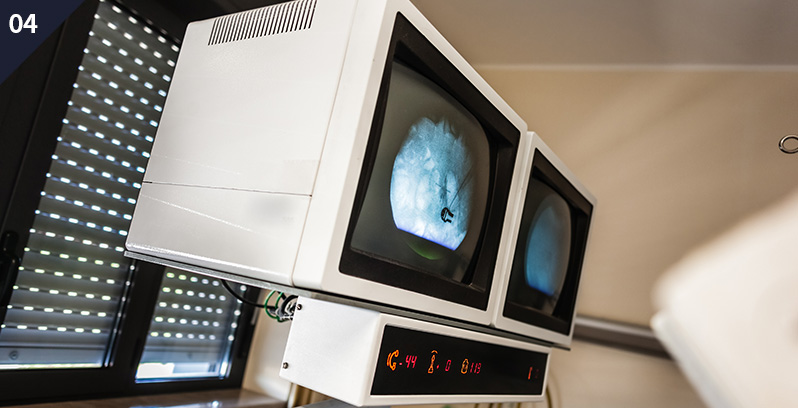

이러한 경우 의심 가능하다!

요 로 결 석 증 상